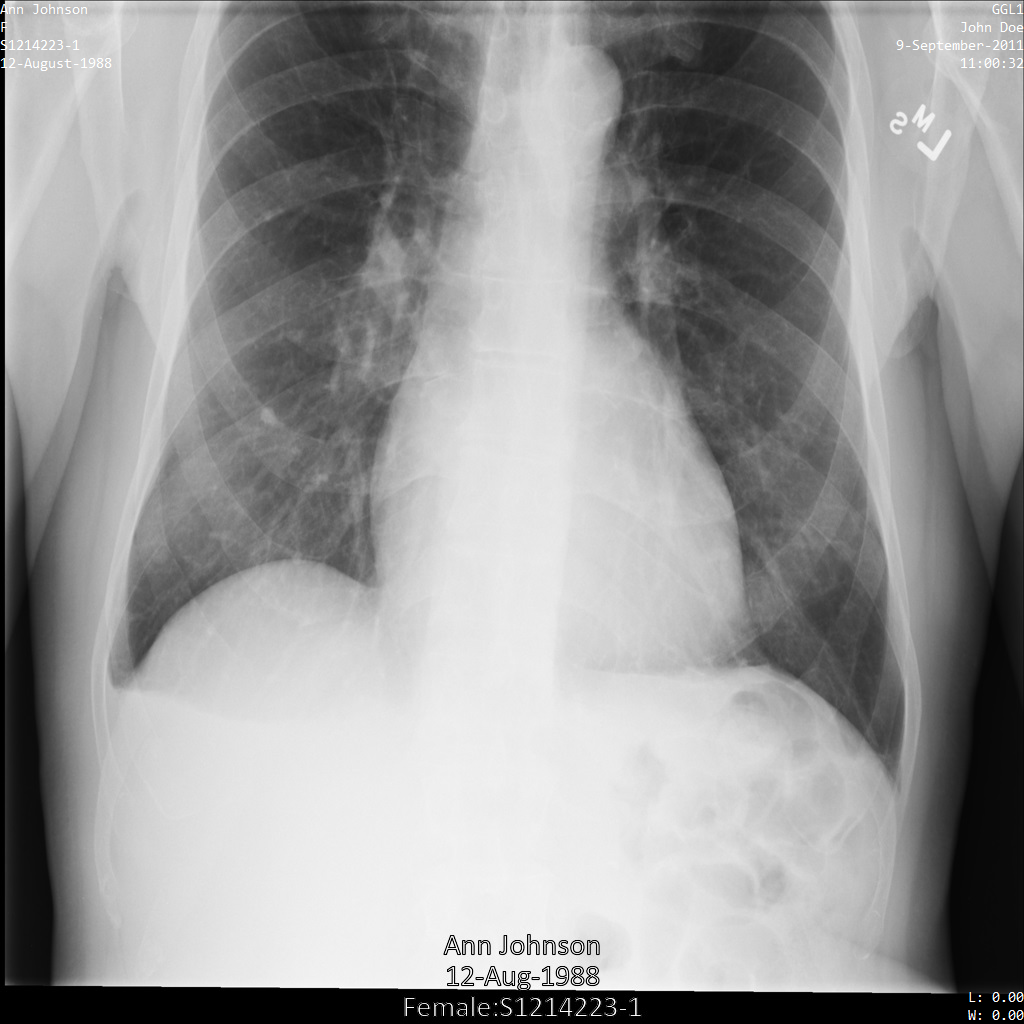

Ciascuna delle sezioni seguenti fornisce esempi di come anonimizzare i dati DICOM utilizzando vari metodi. Con ogni campione viene fornito un output dell'immagine deidentificata. Ogni campione utilizza la seguente immagine originale come input:

Puoi confrontare l'immagine di output di ogni operazione di deidentificazione con l'immagine originale per vedere gli effetti dell'operazione.

Dopo aver inviato l'immagine all'API Cloud Healthcare, l'immagine viene visualizzata come segue. Sebbene i metadati visualizzati negli angoli superiori dell'immagine siano stati oscurati, le informazioni sanitarie protette (PHI) incorporate nella parte inferiore dell'immagine rimangono. Per rimuovere anche il testo integrato, consulta Oscuramento del testo integrato nelle immagini.